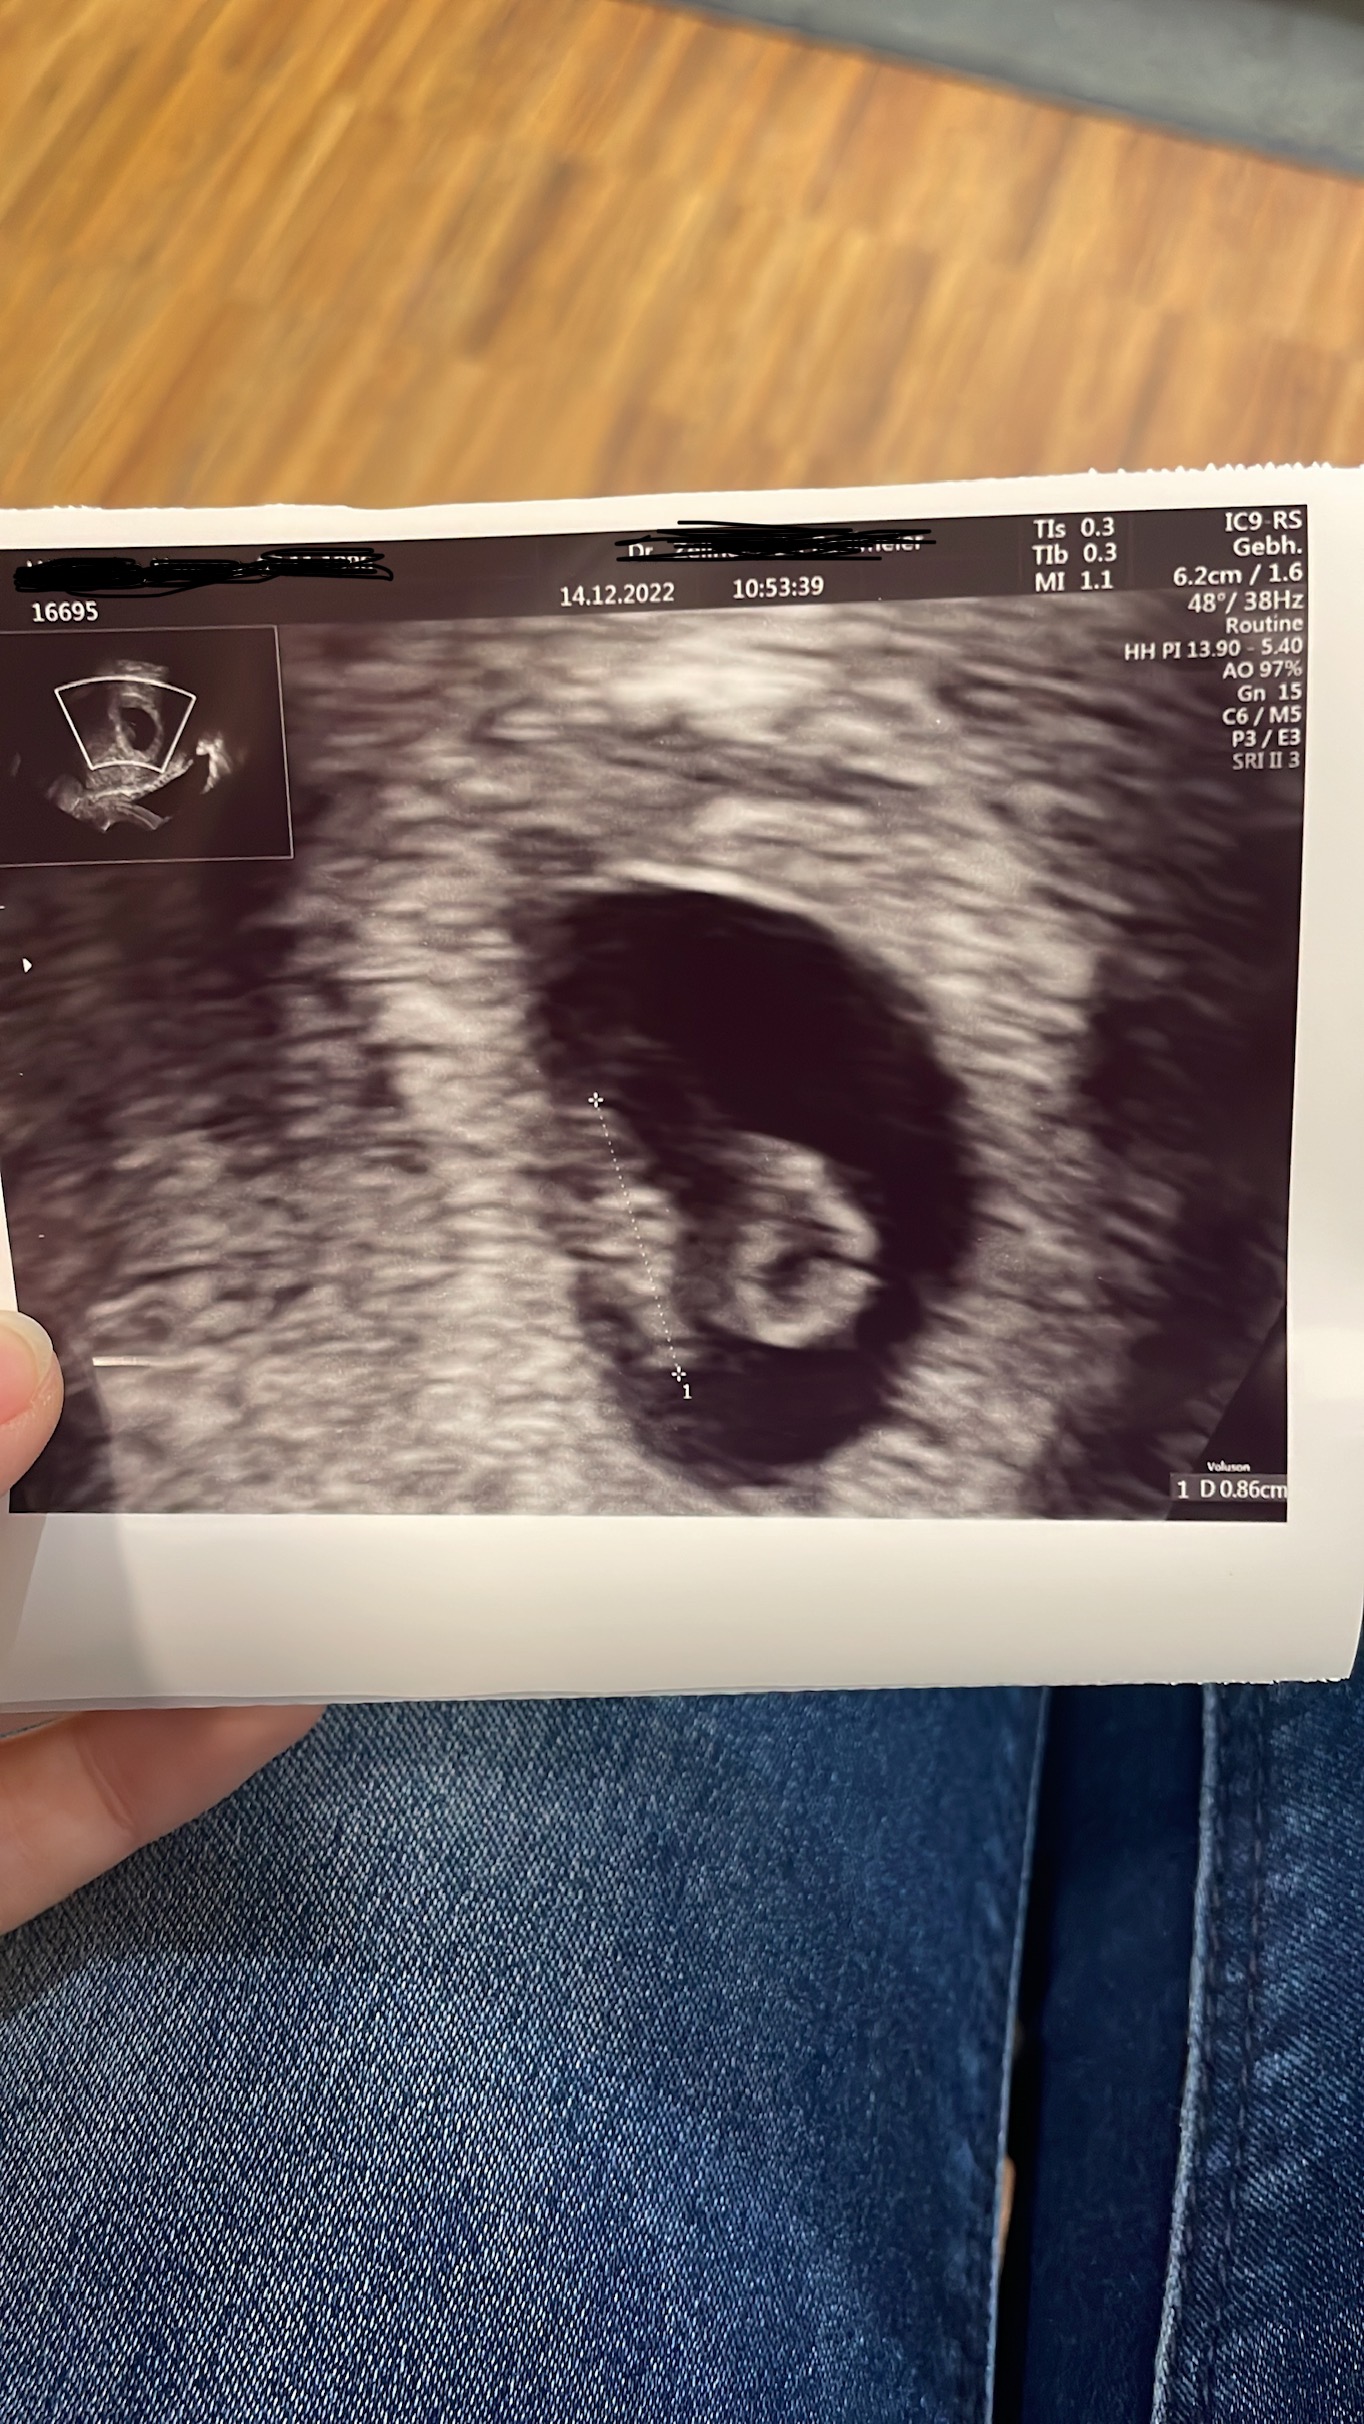

Dem Baby geht es sehr gut, das Herz schlägt super und es ist 0,86cm groß

Nächsten Donnerstag hab ich vor Weihnachten nochmal einen Termin ❤️ die Frauenärztin ist wirklich sehr einfühlsam und nimmt sich die Zeit.